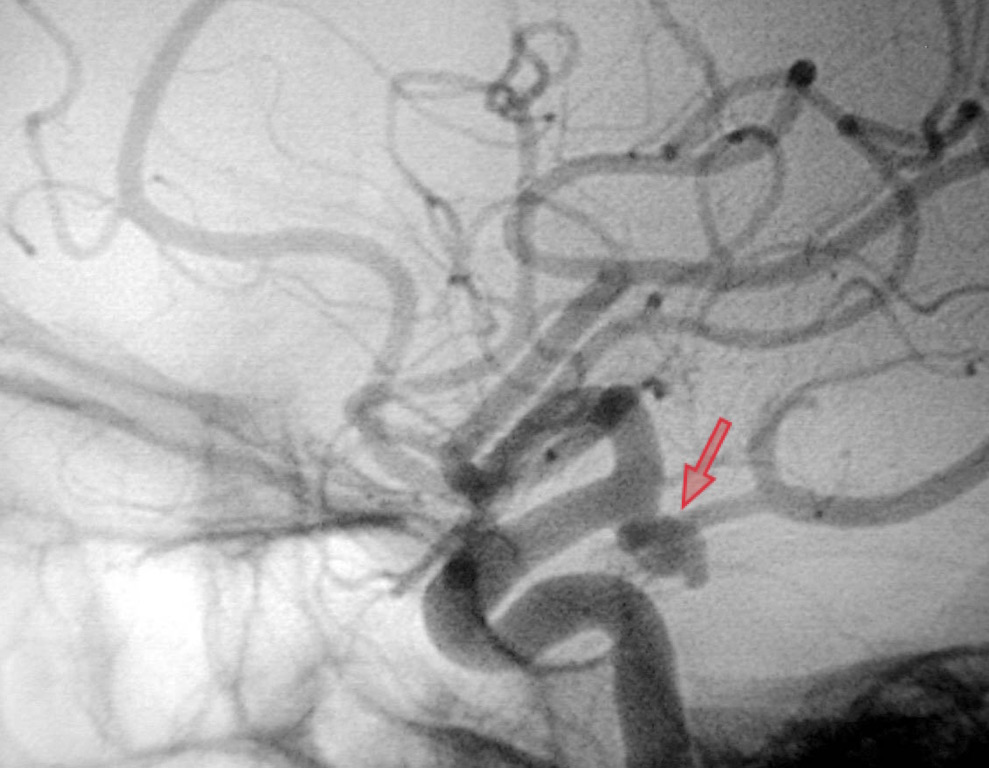

<動脈瘤にカテーテル挿入中>

矢印は動脈瘤

<最後のコイル挿入終了>